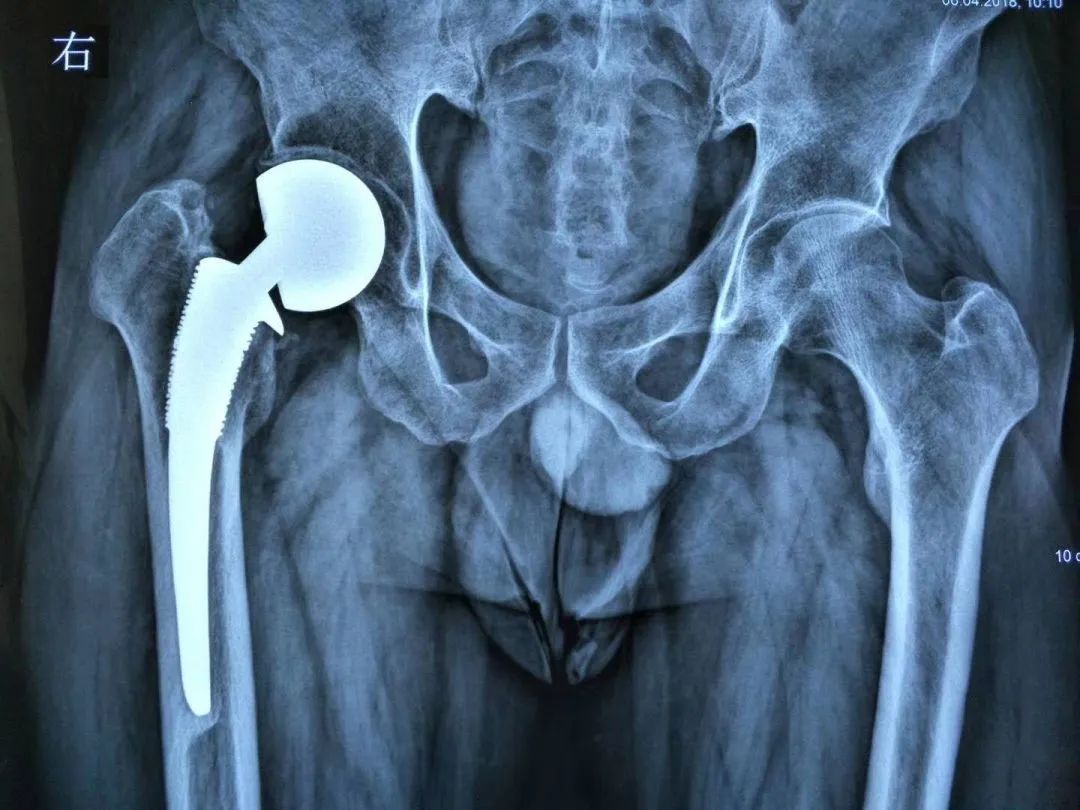

① 股骨侧:可以选择使用一体式的股骨翻修假体来恢复股骨的偏心距,这些假体在拥有多种偏心距可选外,还保持着相同的颈干角,进而能够灵活调整股骨偏距的同时,避免肢体过度延长(图1)。

图1 一体式翻修股骨柄